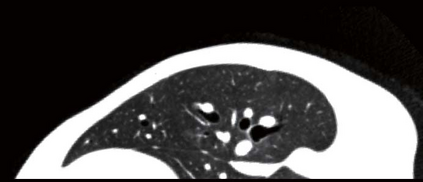

Recent advances in imaging techniques have enabled us to visualize lung tumors or nodules in early-stage cancer. However, the positions of nodules can change because of intraoperative lung deflation, and the modeling of pneumothorax-associated deformation remains a challenging issue for intraoperative tumor localization. In this study, we introduce spatial and geometric analysis methods for inflated/deflated lungs and discuss heterogeneity in pneumothorax-associated deformation. Contrast-enhanced CT images simulating intraoperative conditions were acquired from live Beagle dogs. Deformable mesh registration techniques were designed to map the surface and subsurface tissues of lung lobes. The developed framework addressed local mismatches of bronchial tree structures and achieved stable registration with a Hausdorff distance of less than 1 mm and a target registration error of less than 5 mm. Our results show that the strain of lung parenchyma was 35% higher than that of bronchi, and that subsurface deformation in the deflated lung is heterogeneous.